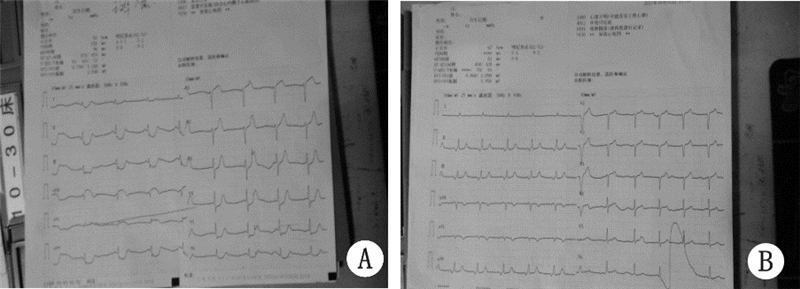

1 资料与方法患者,男,68岁,3年前无明显诱因出现阵发性烧灼样胸骨后疼痛,10~15 min/次,伴有胸闷,气短、大汗,本院诊断为“不稳定性心绞痛”,应用硝酸甘油后症状缓解。此后规律口服阿司匹林、消心痛,上述症状未再发作。入院前3 h无明显诱因出现上述症状,伴有烦躁不安、面色苍白,频繁恶心、呕吐,上腹胀痛,含服硝酸甘油上述症状未缓解。查体:P 54次/min,BP 64/47 mmHg(1 mmHg=0.133 kPa)。面色苍白、皮肤湿冷。神志清,反应迟钝。双肺呼吸音清,未闻及干湿啰音。心率:54次/min,律齐。心电图(图 1A):ST段 aVL导联上抬0.1 mV,Ⅰ、Ⅱ、Ⅲ、aVF、V4-V6导联下移0.1~0.3 mV,aVR导联上移0.2 mV。肌钙蛋白I 27.16 ng/mL。诊断:急性心肌梗死,考虑左主干病变,心源性休克。治疗:常规用药包括:肝素抗凝、可定调脂、多巴胺升压。抗血小板治疗:阿司匹林首剂量300 mg,维持量100 mg/d口服,波立维首剂量600 mg/d,维持量75 mg/d口服;术后常规应用替罗非班静点36 h。急诊冠状动脉造影:左主干末端至左前降支近段95%狭窄,见血栓影,血流TIMI 1级,左回旋支近段100%闭塞,考虑为慢性闭塞,血流TIMI 0级,右冠状动脉弥漫性病变,最窄处50%狭窄,可见侧枝循环向左回旋支供血,血流TIMI 3级(图 2A)。决定行急诊PCI:送6FEBU3.5 指引导管至左冠开口,送Runthrough导丝通过病变处到达前降支远端,再送2.0 mm×15 mm迪马克球囊至前降支至左主干病变处,以12 atm×5″由远至近进行扩张3次,造影示左主干至前降支病变处残余狭窄80%,血流TIMI 2~3级,送乐普3.5 mm×36 mm支架不能通过病变处,送BMW导丝通过病变处,再送乐普3.5 mm×36 mm支架至左主干至前降支病变处,以16 atm×5″进行扩张,释放支架,造影示支架释放满意,无夹层及残余狭窄,血流TIMI 3级(图 2B)。左回旋支病变暂不处理。结果:术后患者胸痛缓解,血压、心率恢复正常。心电图:6 h内aVL导联ST段回降,V3-6导联ST段回到基线(图 1B)。

| 图 1 患者发病时的心电图(A)和PCI术后6 h心电图(B) |